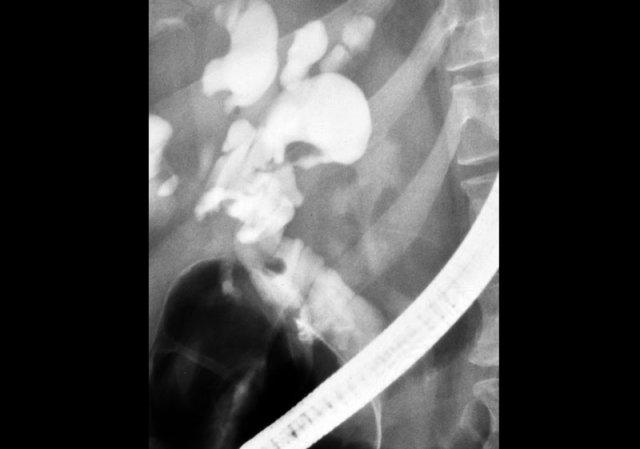

ERCP: Bệnh Caroli với giãn ống mật trong gan nặng. Không có tắc nghẽn. Giãn nhẹ ống mật chủ do viêm đường mật

Bệnh Caroli (4)

Chụp đường mật đóng vai trò quan trọng trong quá trình đánh giá những bệnh nhân này, vì cần phải loại trừ tình trạng tắc nghẽn.

Điều này có thể được thực hiện bằng MRCP hoặc ERCP, như được minh họa bên trái.

Không có dấu hiệu tắc nghẽn.

Giãn nhẹ ống mật chủ là kết quả của viêm đường mật.